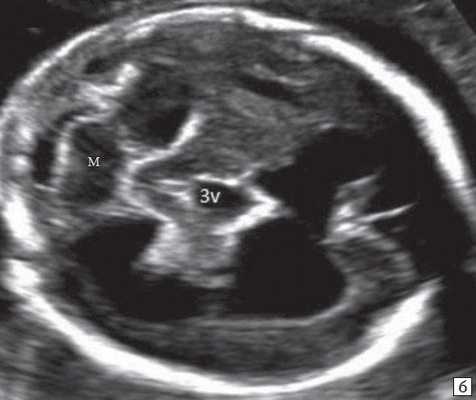

Анализ сохраненных трехмерных изображений позволил получить более детальные характеристики структур мозга плодов с РЭС. На среднесагиттальном срезе в наблюдениях 1, 2 и 4 (в наблюдении 3 получить качественно этот срез не удалось) отмечено наличие атипичной полукруглой формы шатра (fastigium) 4-го желудочка, гипоэхогенная структура мозжечка с контрастирующим наружным контуром (рис. 3). При этом в первых трех наблюдениях отмечено полное отсутствие структур червя, тогда как в наблюдении 4 по контуру 4-го желудочка выявлены гиперэхогенные структуры, расцененные как передние отделы червя. Наличие передних отделов червя отражает и ряд послойных срезов в режиме TUI (рис. 4). У плода в наблюдении 4 также обращает на себя внимание относительное расширение надмозжечковой цистерны, с линейными структурами, при нормальной ориентации намета мозжечка (рис. 4).

а) Наблюдение 2, 3D. На эхограмме: 1 - боковой желудочек, 3v - 3-й желудочек, стрелки - контур мозжечка, пунктирная линия - шатер.

б) Наблюдение 4. На эхограмме: М - мозжечок.

Отсутствие червя выражается однородной гипоэхогенной картиной структуры мозжечка, что видно на стандартных аксиальных срезах при УЗИ. Среднесагиттальный срез (в наших наблюдениях этот срез был получен при трехмерной реконструкции) головного мозга плода показывает гипоэхогенный практически однородный мозжечок, что свидетельствует об отсутствии исчерченности червя, с четко контрастирующей картиной коры. Здесь же видно и отсутствие типичной картины 4-го желудочка с полукруглой формой шатра. Только в наблюдении 4 нами были отмечены фрагменты передних отделов червя мозжечка в проекции стыка водопровода и 4-го желудочка.